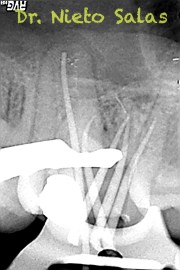

No es habitual en nuestra práctica casos como estos, pero os pongo algunos más:

Una vez desobturados los conductos, empezamos a hacer una endodoncia convencional.

También, este caso tiene particular interés, porque he conseguido una foto (no sé de donde, perdone al autor), que es muy similar en un diente diafanizado.